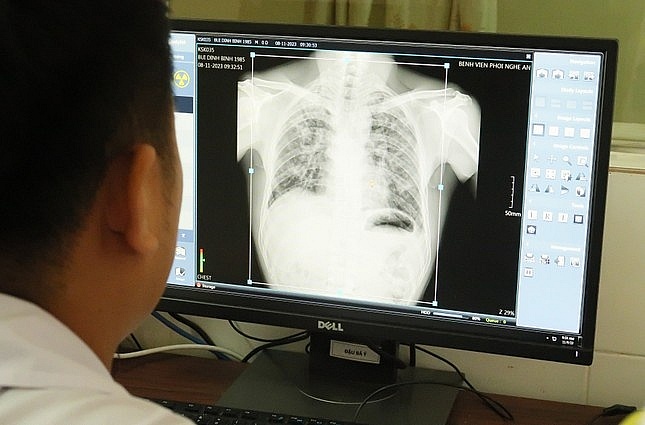

Trong ngày đầu tiên đoàn đã thăm khám, chụp phim cho các công nhân. Kết quả khám lâm sàng cho thấy, một số công nhân có dấu hiệu khó thở, chụp X-Quang phổi bị trắng phần lớn và có chấm trắng.

![]() |

| Ảnh chụp phổi của một công nhân trong buổi thăm khám. Ảnh: tienphong.vn |

"8/9 người được Viện Sức khỏe nghề nghiệp xác định là mắc các bệnh liên quan đến bụi phổi nghề nghiệp", bác sĩ Lâm nói và đồng thời cho biết trong trường hợp kết quả chụp phim phát hiện mắc bụi phổi, đoàn kiểm tra sẽ tổng hợp và gửi phim cho Viện Sức khỏe nghề nghiệp và Môi trường để hội đồng chuyên môn đánh giá các bước tiếp theo nhằm xác nhận bệnh nghề nghiệp cho các công nhân.